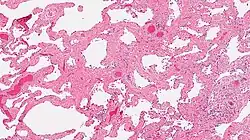

Smoking-related interstitial fibrosis (SRIF)

A photomicrograph of SRIF as seen by a pathologist through a microscope. The tissue on the slide is stained with two standard dyes (hematoxylin: blue, eosin: pink) to make it visible. . Note that the excess collagen in SRIF gives the air sacs a pink color.

Smoking-related interstitial fibrosis (SRIF) is an abnormality in the lungs characterized by excessive collagen deposition within the walls of the air sacs (interstitial fibrosis). This abnormality can be seen with a microscope and diagnosed by pathologists. It is caused by cigarette smoking.[1][2]

The defining feature of smoking-related interstitial fibrosis is a distinctive/unique type of fibrosis characterized by "ropey" collagen bundles within the walls of the air sacs (alveoli), almost always in association with other smoking-related abnormalities such as pigmented macrophages and emphysema.[6]